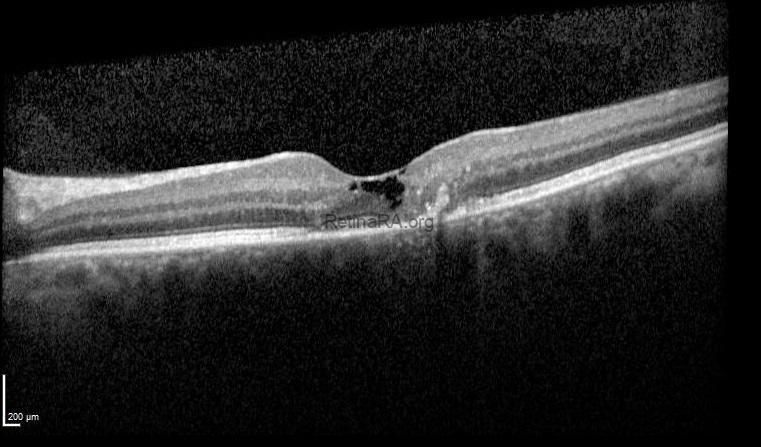

Optical coherence tomography demonstrated focal disruption of the ellipsoid zone and external limiting membrane, intraretinal hyporeflective cavities, hyperreflective foci with posterior shadowing, and an inner limiting membrane (ILM) drape sign.

These findings were consistent with macular telangiectasia type 2.

Macular telangiectasia type 2 (MacTel 2) is a bilateral, slowly progressive neurodegenerative macular disease that often remains underdiagnosed in routine practice. Patients may present with relatively preserved visual acuity despite complaints of reading difficulty, paracentral scotomas, or metamorphopsia. Funduscopic findings are typically subtle and include parafoveal loss of retinal transparency, right-angled venules, and pigment clumping in later stages. Optical coherence tomography plays a key role in diagnosis, demonstrating inner retinal cavitations, disruption of the ellipsoid zone and external limiting membrane, and the characteristic ILM drape sign. Recognition of these early structural changes is essential, as MacTel 2 is frequently mistaken for more common macular pathologies. Careful multimodal imaging allows timely diagnosis, appropriate counseling, and follow-up for potential neovascular complications.